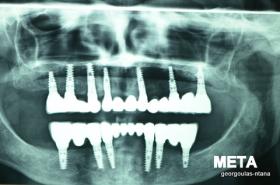

ΟΛΙΚΗ ΑΠΟΚΑΤΑΣΤΑΣΗ ΑΝΩ Κ ΚΑΤΩ ΓΝΑΘΟΥ ΜΕ ΕΜΦΥΤΕΥΜΑΤΑ, ΑΜΕΣΗ ΦΟΡΤΙΣΗ Κ ΑΝΟΙΚΤΗ ΑΝΥΨΩΣΗ ΙΓΜΟΡΕΙΟΥ

Η ασθενής αυτή είχε παλιές ακίνητες αποκαταστάσεις (γέφυρες) στην άνω γνάθο  κ μια κινητή προσθετική αποκατάσταση (μερική οδοντοστοιχία-"μασελάκι") στην κάτω γνάθο. Ήταν δυσαρεστημένη τόσο με την εμφάνιση όσο και με τη λειτουργία των δοντιών της καθώς παραπονιόταν ότι  είχαν εντονη κινητικότητα ενώ και οι προσθετικές τους εργασιές δεν ήταν σταθερές. Η πρόγνωση των δοντιών κρίθηκε φτωχή με αποτέλεσμα να μην είναι δυνατή η συμμετοχή τους σε μια νεα προσθετική αποκατάσταση με μακροχρόνια διάρκεια. Η ασθενής επιθυμούσε οι νέες αποκαταστάσεις να είναι σταθερές και ακίνητες.  Για το λόγο αυτό αποφασίστηκε η ολική αποκατάσταση της άνω κ κάτω γνάθου με ακίνητες επιεμφυτευματικές εργασίες. Στην αριστερή πλευρά της άνω γνάθου, λόγω μη επαρκούς οστού για την τοποθέτηση εμφυτευμάτων προηγήθηκε επέμβαση ανοιχτής  ανύψωσης ιγμορείου άντρου με τη χρήση πιεζοχειρουργικού μηχανήματος ώστε να δημιουργηθεί το κατάλληλο οστικό υπόστρωμα. Ακολούθησε σε επόμενο χειρουργείο η εξαγωγή των υπάρχοντων δοντιών κ η άμεση τοποθέτηση εμφυτεύματων (άμεση εμφύτευση) κ δύο μέρες μετά η τοποθέτηση προσωρινής εργασίας επί των εμφυτευμάτων (άμεση φόρτιση) με αποτέλεσμα η ασθενής να μη μείνει καθόλου χωρίς δόντια κ να είναι καλυμένη αισθητικά όσο καιρό διήρκησε η εργασία